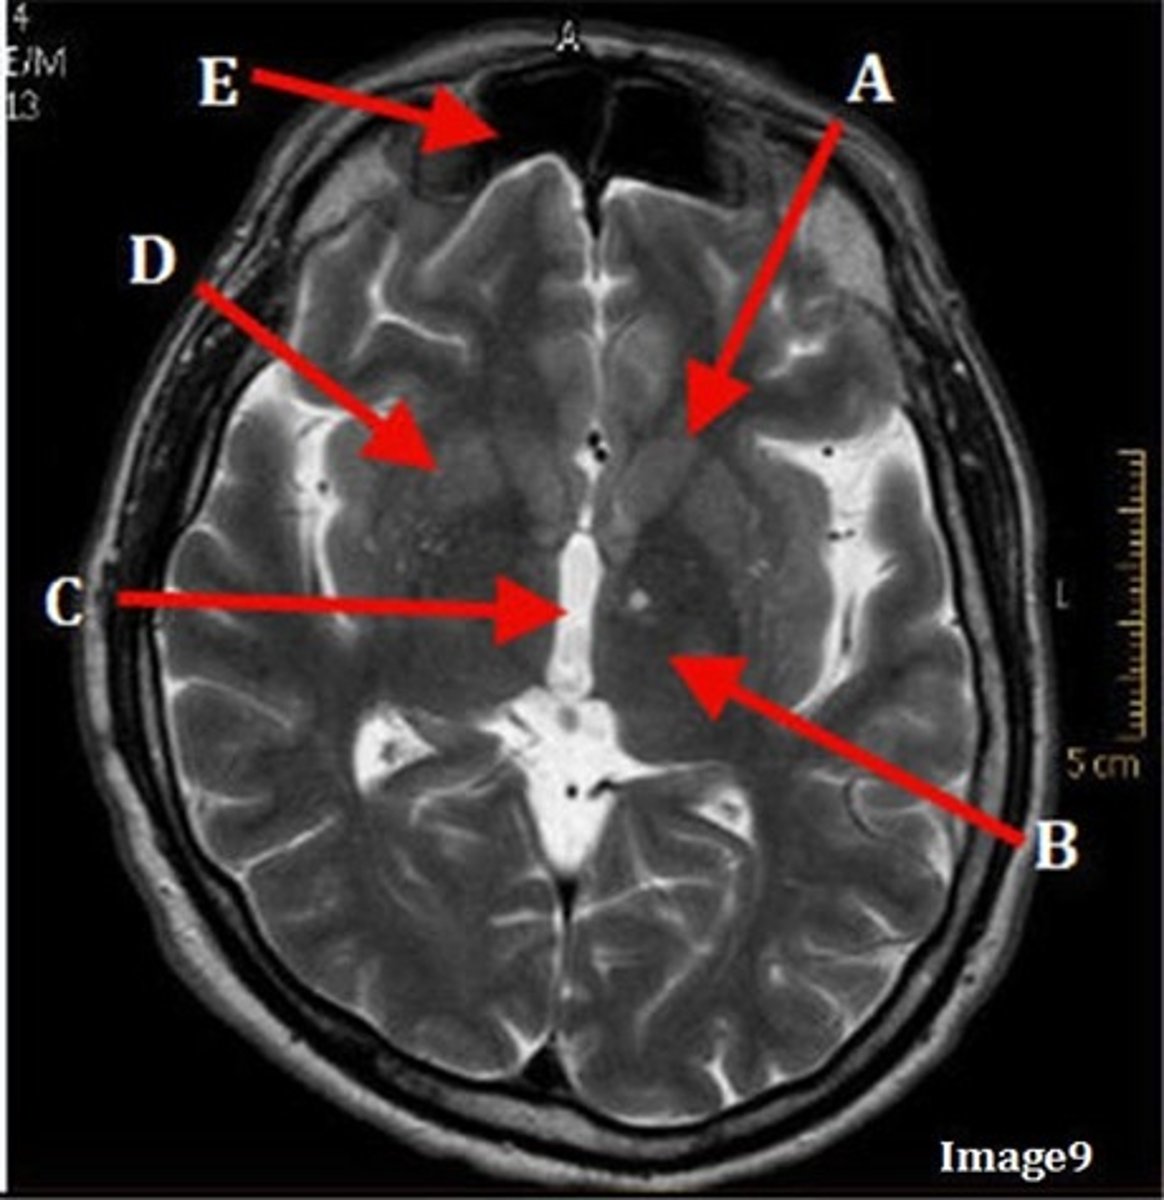

A (region)

dark band is called?

basal ganglia region

internal capsule

B

posterior horn of lateral ventricle

C

anterior horn of lateral ventricle

D

white matter

caudate nucleus

F

lentiform nucleus

E

gray matter